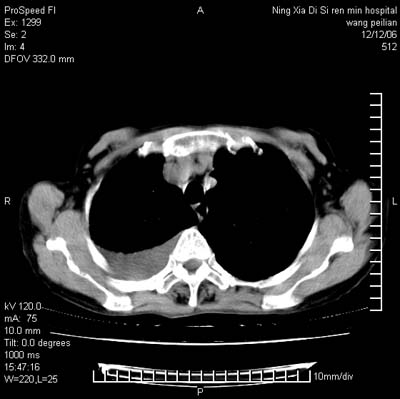

标题: CT5609:胸部:女77 病史不详 [打印本页]

标题: CT5609:胸部:女77 病史不详

两肺可见多个大小不等的结节,左侧有胸水,纵隔淋巴结增大,考虑是细支气管肺泡癌

两肺尖纤维索状影,两下肺结节块状影,且有钙化灶,右胸腔积液。考虑肺结核并胸膜炎。

两肺尖纤维索状影,两下肺结节块状影,且有钙化灶,右胸腔积液。考虑肺结核并胸膜炎肺间质纤维化

两肺以间质性病变为主,并有胸腔积液,考虑结核

考虑:1、慢性支气管炎合并全小叶型肺气肿、间质纤维化;

2、双肺结核;

3、右侧胸膜炎(积液)。

考虑两肺结核,右侧胸膜炎(积液)

双肺见多个结节状及条索状影,双侧胸腔积液,右侧叶间积液,考虑结核性胸膜炎

肺结核并右侧结核性胸膜炎